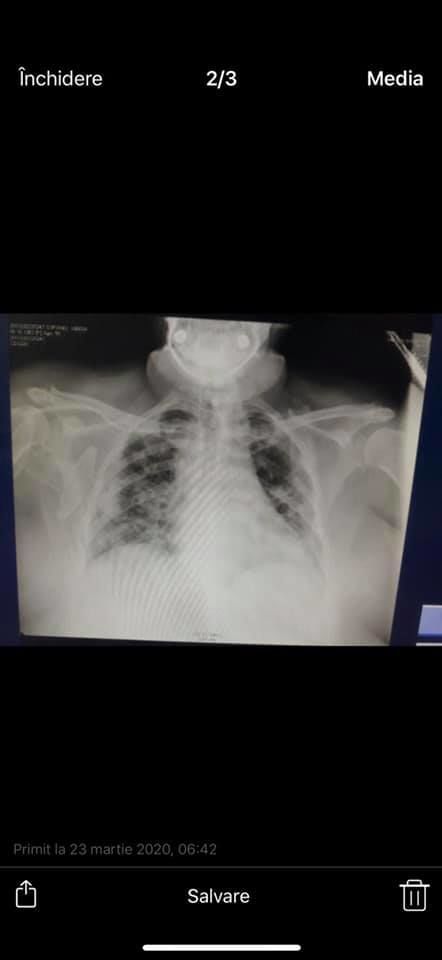

Știți ce-s cu pozele de mai jos? Raportul zilnic al medicilor reanimatologi-anesteziologi din terapia septică, unde stau internați pacienții gravi cu COVID-19. Zilnic, de la 06:00 dimineață, profesorul Anatol Ciubotaru primea radiografiile fiecărui asemenea pacient, le compara cu radiografiile din seara precedentă și discuta cu medicii tacticile de tratament în continuare, de ce au nevoie pacienții și medicii.

Pozele din viber din telefonul tatei, el nu știe că le postez și sper că nu încalc nimic, parcă nu-s date cu caracter personal după care să poată fi identificați pacienții. Pozele date au fost trimise de medicul de gardă dimineața când avea deja febră, dar era la datorie. El este un erou. Să avem grijă de eroii noștri... Profesorul Ciubotaru nu mai poate să o facă deja, iar premierul a promis că fără el se va îmbunătăți brusc situația epidemiologică în spital”, a explicat tânăra pe o rețea de socializare.